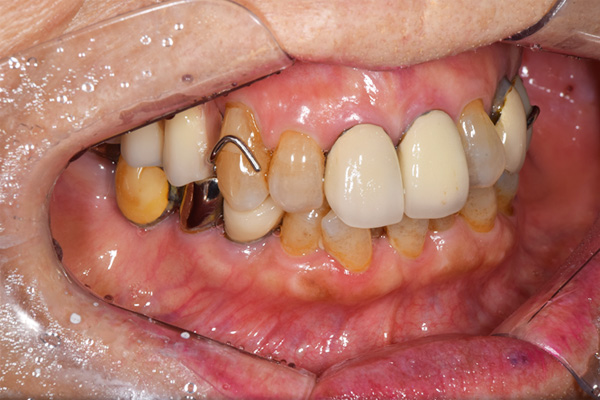

前歯が折れて当院にいらっしゃいました。 過去に下の入れ歯を作ったが、合わなくなってずっと入れ歯をいれていらっしゃらない患者様でした。 これは奥歯で噛むことができないため、前歯で噛むことを繰り返したために、負担に耐えられなくなった前歯が折れてかぶせ物ごと 外れてしまったのだと考えられます。 痛くない、違和感の少ない、下の入れ歯を作ることがこの方のゴールであると考えられました。

金属を使用して、薄く違和感が少ない入れ歯が完成しました。 また、見た目にも気を使い、バネが見えにくい様な構造にしました。

入れ歯をお口の中にいれた状態です。前歯もMTMといって、歯を少し引っ張り出す処置を行なったことで、しっかり残せて、またかぶせ物をしました。

義歯は下顎で、しっかり噛めること、違和感の少ないものという希望があったため、なるべく入れ歯を薄く作成するために金属をしようした義歯とした。

また、見た目もあまり義歯が目立たない様に、バネの部分を見えにくいように作成した。